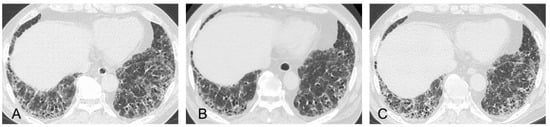

- Suzuki, A.; Sakamoto, S.; Kurosaki, A.; Kurihara, Y.; Satoh, K.; Usui, Y.; Nanki, T.; Arimura, Y.; Makino, H.; Okada, Y.; et al. Chest high-resolution CT findings of microscopic polyangiitis: A Japanese first nationwide prospective cohort study. AJR Am. J. Roentgenol. 2019, 213, 104–114. [Google Scholar] [CrossRef]

- Yamakawa, H.; Sato, S.; Nakamura, T.; Nishizawa, T.; Kawabe, R.; Oba, T.; Horikoshi, M.; Akasaka, K.; Amano, M.; Kuwano, K.; et al. Prognostic value of radiological findings indeterminate for UIP pattern and anterior upper lobe honeycomb-like lesion in chronic fibrosing interstitial lung disease associated with MPO-ANCA. BMC Pulm. Med. 2021, 21, 346. [Google Scholar] [CrossRef] [PubMed]

- Yamakawa, H.; Ogura, T.; Sato, S.; Nishizawa, T.; Kawabe, R.; Oba, T.; Kato, A.; Horikoshi, M.; Akasaka, K.; Amano, M.; et al. The potential utility of anterior upper lobe honeycomb-like lesion in interstitial lung disease associated with connective tissue disease. Respir. Med. 2020, 172, 106125. [Google Scholar] [CrossRef] [PubMed]

- Silva, C.I.; Müller, N.L.; Hansell, D.M.; Lee, K.S.; Nicholson, A.G.; Wells, A.U. Nonspecific interstitial pneumonia and idiopathic pulmonary fibrosis: Changes in pattern and distribution of disease over time. Radiology 2008, 247, 251–259. [Google Scholar] [CrossRef]